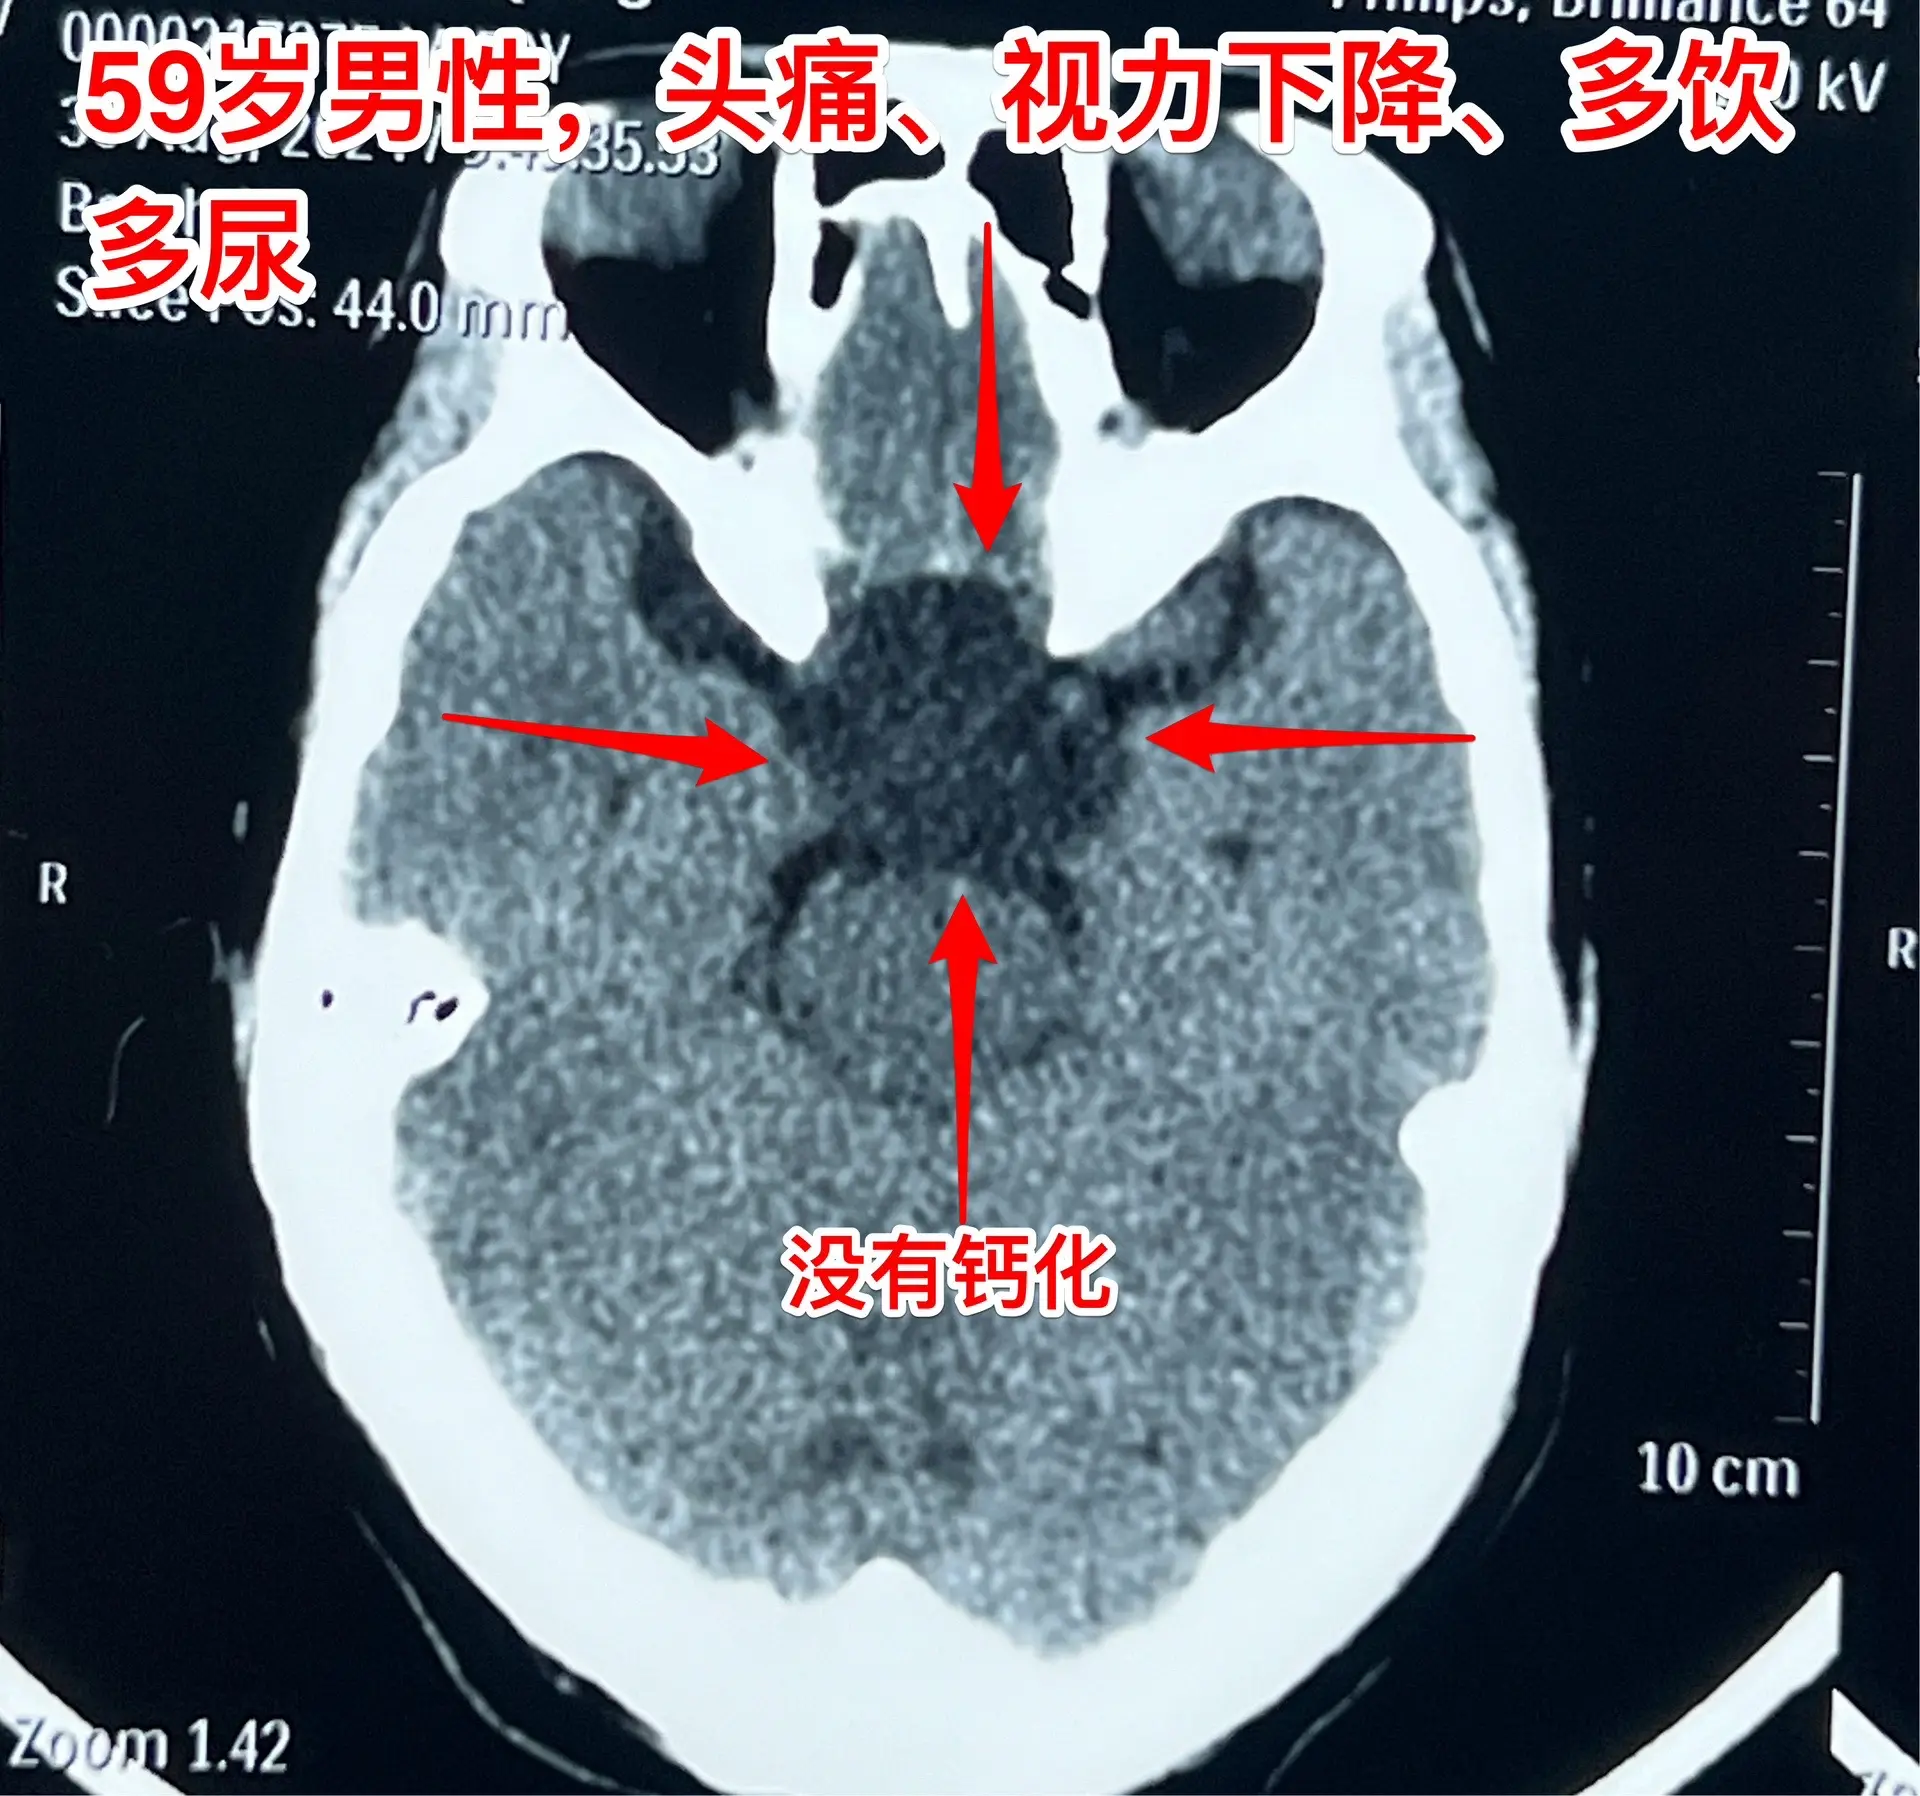

头痛、视力下降、多饮多尿、体重下降。59岁洛阳市男性,近三年感头痛,近一年半感觉视力下降,以为是老花眼,未就医。近9个月多饮多尿,夜间睡眠很差,白天精神很差。近半年体重下降25斤。 2024.8.23到医院就诊,作头部磁共振发现颅咽管瘤。2024.9.5在我科行开颅手术切除颅咽管瘤。手术中发现肿瘤是囊性的,内壁有瘤结节,没有钙化,所以是乳头型颅咽管瘤,肿瘤得到完全切除。手术后双眼视力显著改善。(今年的第133例颅咽管瘤)